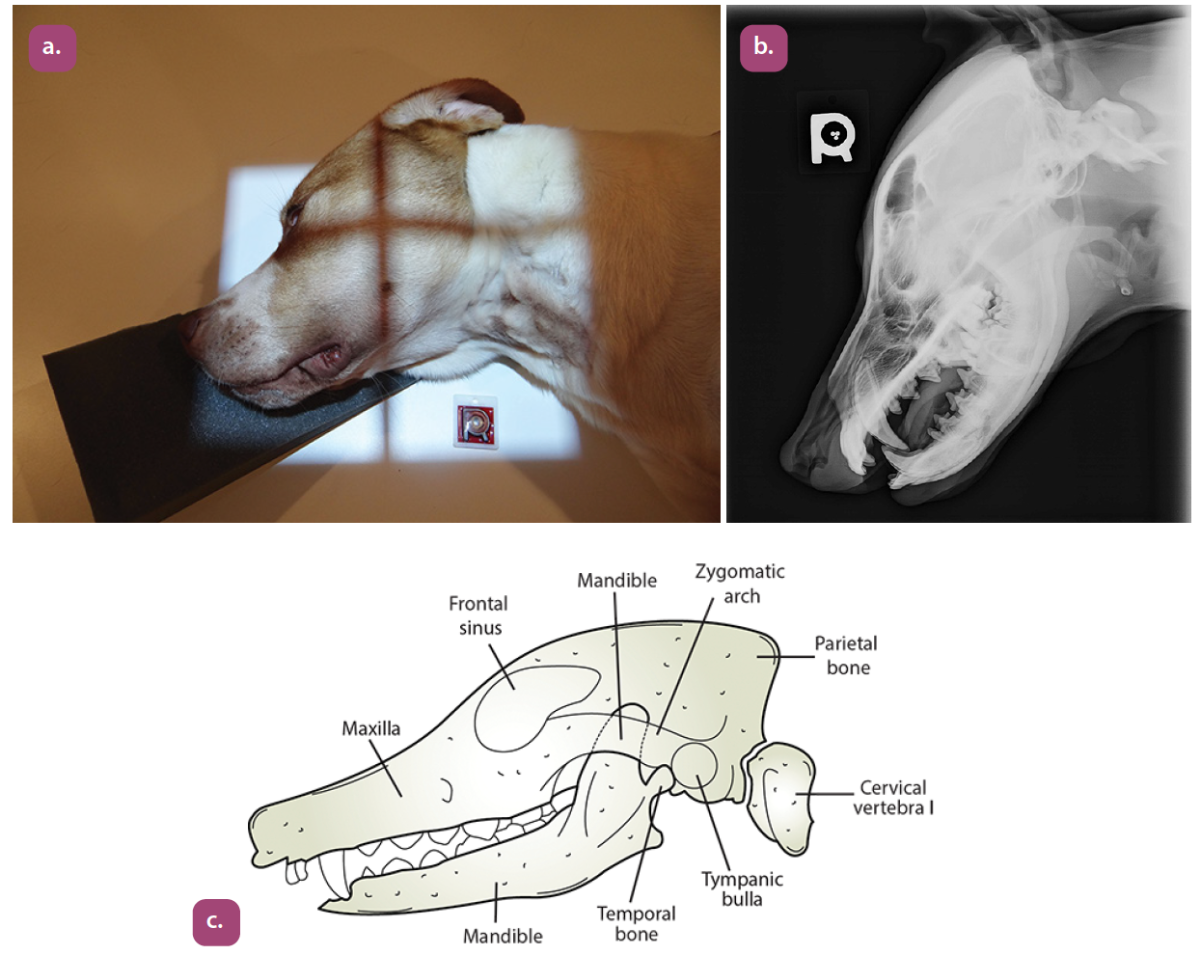

lateral projection of the skull